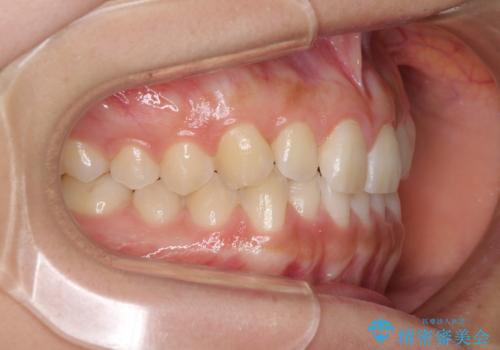

- 前歯の叢生と、奥歯の咬み合わせの悪さを気にして来院された患者様です。

左下には後続永久歯の欠損した乳歯が残存しており、叢生を相まって咬合関係が乱れていました。

乳歯は抜歯し、インビザラインにて矯正治療を行いながら、並行してインプラントによる補綴治療を行うこととしました。